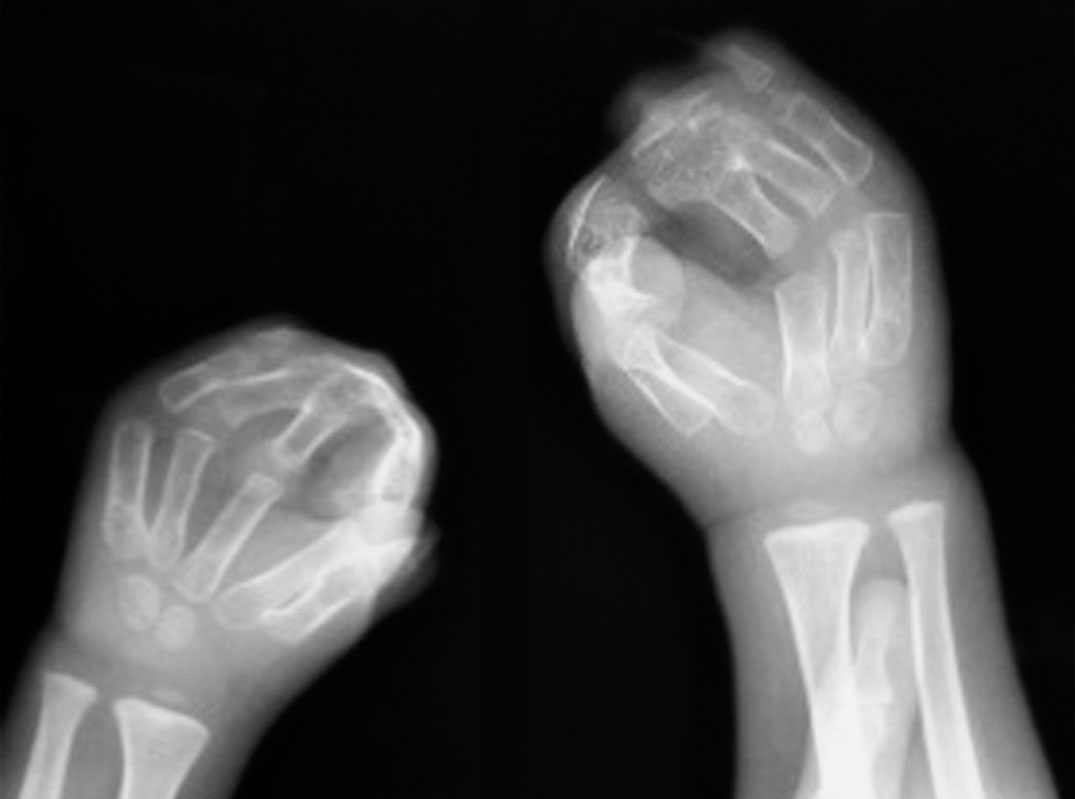

4)拳击手:包括Apert 综合征(图1-2-26)。

图1-2-26 Apert 综合征指骨末端骨性融合